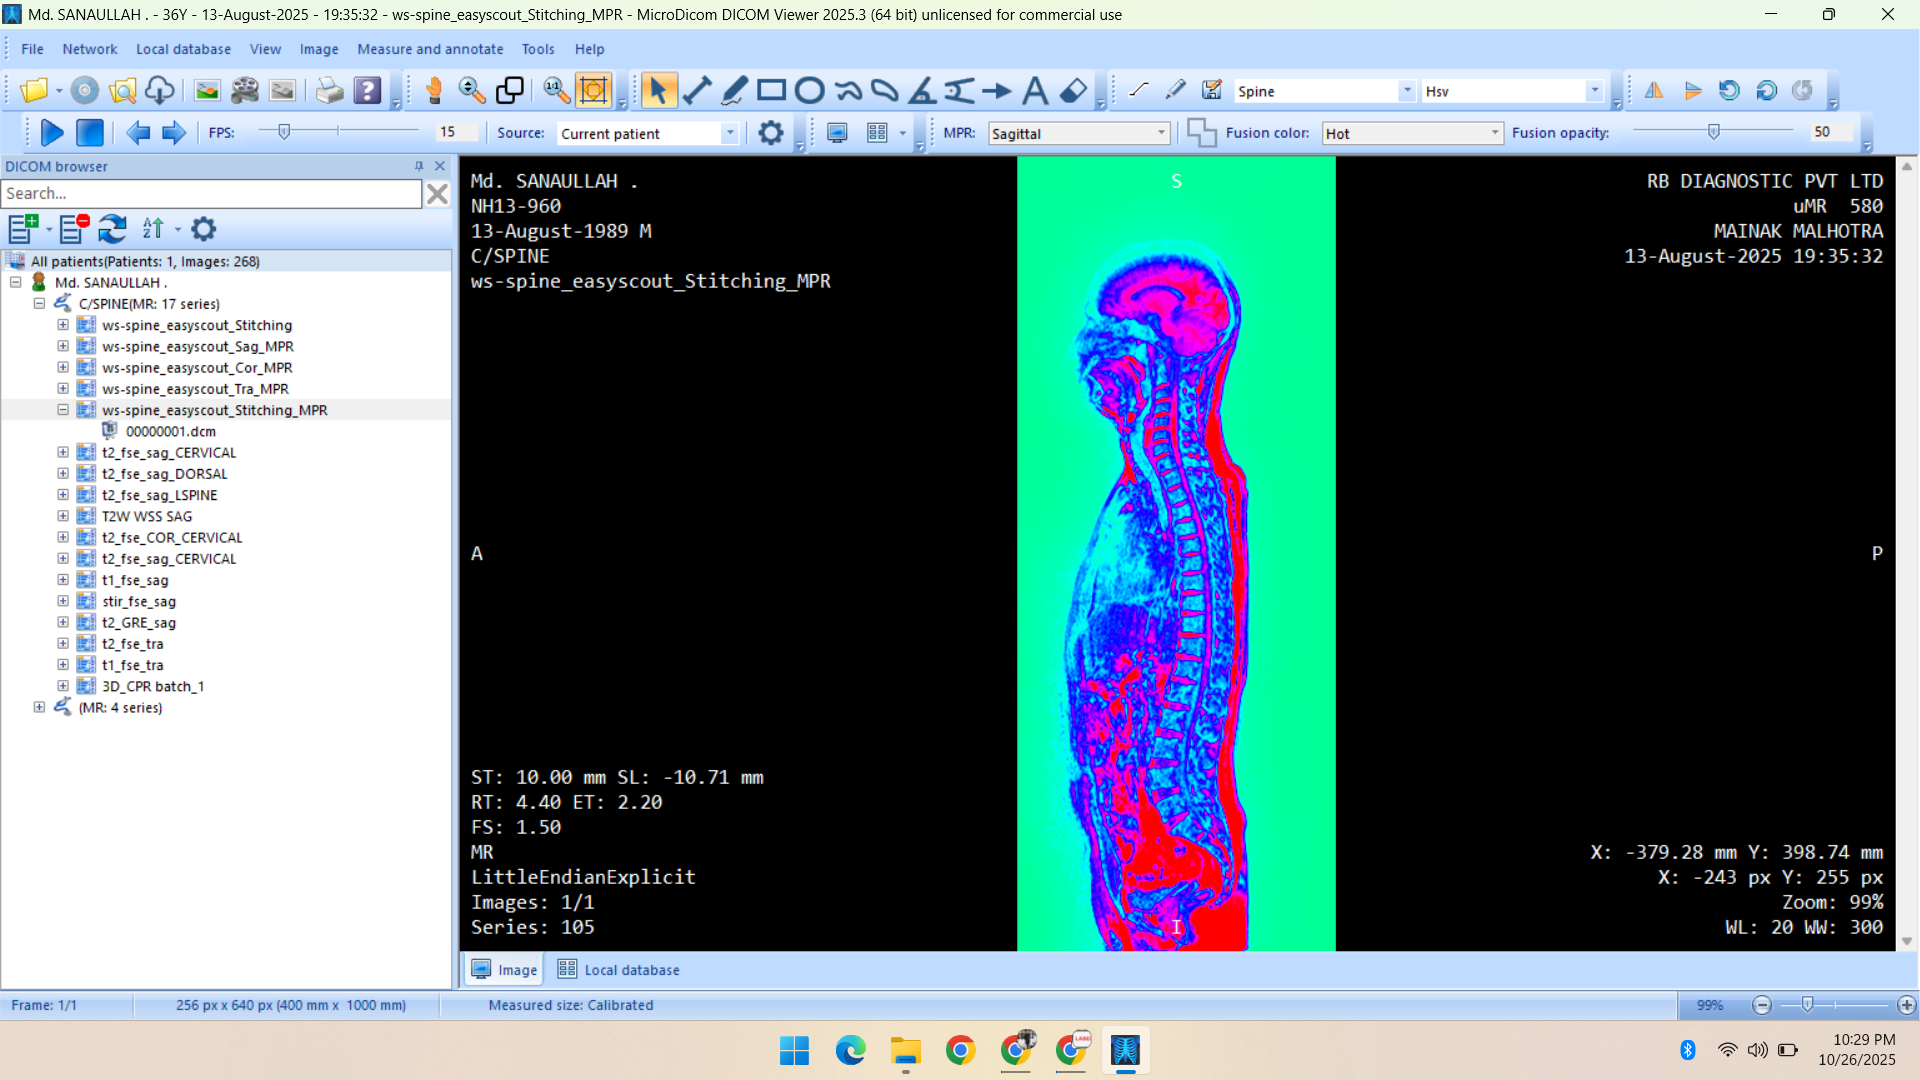

- Radiology Data – CT Scans, X-Rays, MRI, Echocardiography, Ultrasound.

Healthcare & Medical Data Supply

We specialize in healthcare datasets including radiology (CT, X-ray, MRI, Ultrasound, Echocardiography), pathology microscopy, and histopathology images — all ethically sourced and research-ready.

Portfolio

Showcasing Innovative AI Solutions and Data Services: Delivering Quality Data for Smarter, Future-Ready Applications

- MRI